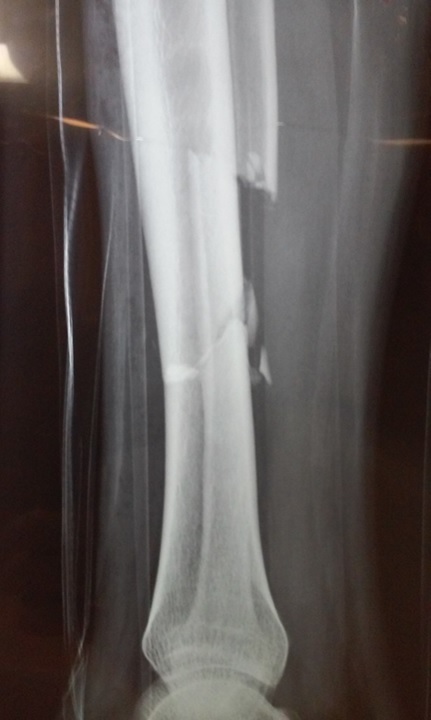

Radriografías de inicio:

Revaloración 14.11.15 9 hrs

Paciente masculino que se encuentra cursando sus primeras 6 horas de ingreso en esta unidad médica con diagnóstico de fractura diafiaria de tibia izquierda 42 B2.1 de AO, el cual a la exploración  física se encuentra con dolor intenso en toda la extremidad, el cual se incrementa a la manipulación    en flexo extensión,  aumento de volumen de la extremidad, edema  a tensión,  además de alteraciones en la sensibilidad (parestesias) y llenado capilar retardado; así como presencia de lesiones dérmicas tipo flictenas de predominio en cara anterior y medial de tibia izquierda.

Clínicamente con datos compatibles con síndrome compartamental de extremidad pélvica izquierda.

FRACTURA DE TIBIA Y PERONE

(Caso Hipotético)

PADECIMIENTO ACTUAL

´  Refiere iniciar su padecimiento actual el 12/11/15 al ser atropellado por automóvil con contusión en extremidad pélvica derecha, lo que condiciona dolor inmediato en pierna, deformidad y limitación funcional.

´  Extremidades pélvicas asimétricas, a expensas de la derecha, la cual se encuentra con deformidad a nivel de unión de tercio medio con distal, dolor a la palpación, crepitación, sin datos de compromiso neurovascular distal, arcos de movilidad de rodilla y tobillo limitados, secundario a dolor.

IMPRESIÓN DIAGNOSTICA

´  Fractura diafisaria de tibia y peroné derechos, 42 a2.2 de AO